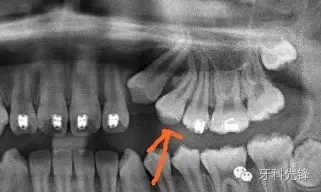

正畸需要拔除的牙齒

拔牙斷根了怎么辦?

口腔里面的照片,牙齒位置較高,

從X片上可以發(fā)現(xiàn)根尖1/3約有120°彎曲。